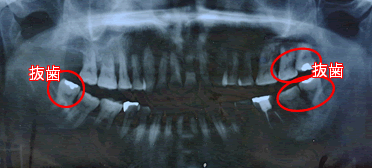

当歯科医院では、完治の可能性が低い(Hopeless)5本の歯は抜歯を行い、歯内療法歯周病治療を中心に残りの26本については歯牙の保存を行っていく治療方針を提示いたしました。

歯周病の初期治療、5本の抜歯、歯周外科による治療。

5本抜歯の後、口腔全体に歯周外科治療をおこなう。白い線の部分は、歯内歯周病変のため、抜随。